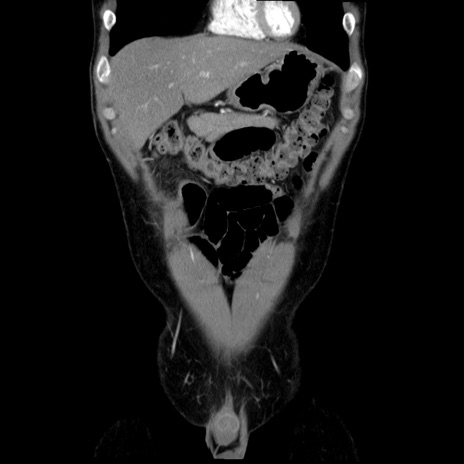

症例36(冠状断像)

【症例】20歳代 男性

【主訴】心窩部痛

【現病歴】今朝より上腹部痛あり。一旦軽快していたが再度出現したため救急要請。昨日夕に白身の魚を含む刺身を食べた。

【身体所見】BP 136/89mmHg、HR 74/min、BT 37.0℃、腹部:膨満、軟、心窩部に圧痛あり。反跳痛なし、筋性防御なし、腸雑音やや亢進あり。

【データ】WBC 17700、CRP 0.48